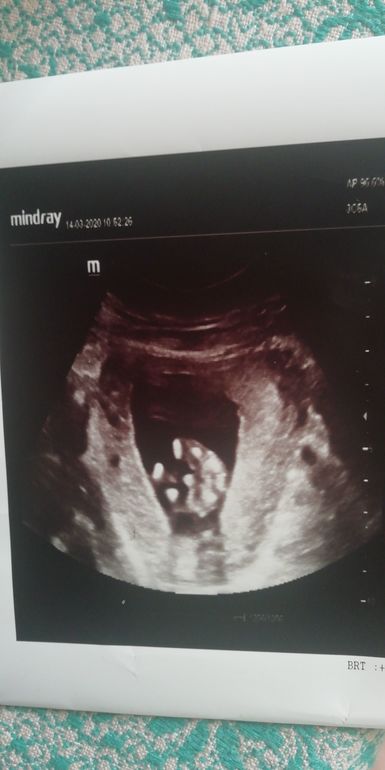

Всем привет. Девчули гляньте пожалуйста пол малыша моего, врачь сказал мальчик вроде бы, а вдруг нет?!